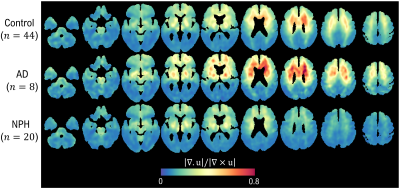

《正常压力脑积水和阿尔茨海默病中的磁共振弹性成像基础可压缩性测量》

Magnetic Resonance Elastography Based Measure of Compressibility in Normal Pressure Hydrocephalus and Alzheimer’s Disease

正常压力脑积水(NPH)和阿尔茨海默病(AD)是两种涉及大脑结构变化的神经退行性疾病。本研究旨在测试一种新的基于磁共振弹性成像(MRE)的组织可压缩性测量方法,并探索其在NPH和AD中的应用。研究者定义了可压缩性测量为MRE波速的比率,并使用T2加权成像和T1加权结构成像来评估两组患者的大脑组织。结果显示NPH和AD在可压缩性测量上呈现出不同的模式,表明MRE测量的可压缩性可能作为一种新的生物标志物,用于区分这两种疾病。研究讨论了MRE测量的可压缩性如何反映大脑组织的物理特性,并提出了这种测量方法在早期诊断和监测NPH和AD进展中的潜在应用。结论强调了MRE测量的可压缩性作为一种有前景的工具,可以揭示NPH和AD中的疾病特异性模式,为未来的研究和临床实践提供了新的视角。

7ecf91fb5332c703f0eecaa326f535ae.png

对照组、阿尔茨海默病(AD)组和正常压力脑积水(NPH)组参与者的可压缩性测量图。与NPH组相比,对照组在脑室周围和大脑顶点方向上的可压缩性测量值更高。

在AD组与NPH组的比较中也观察到了类似的趋势,但差异更大。